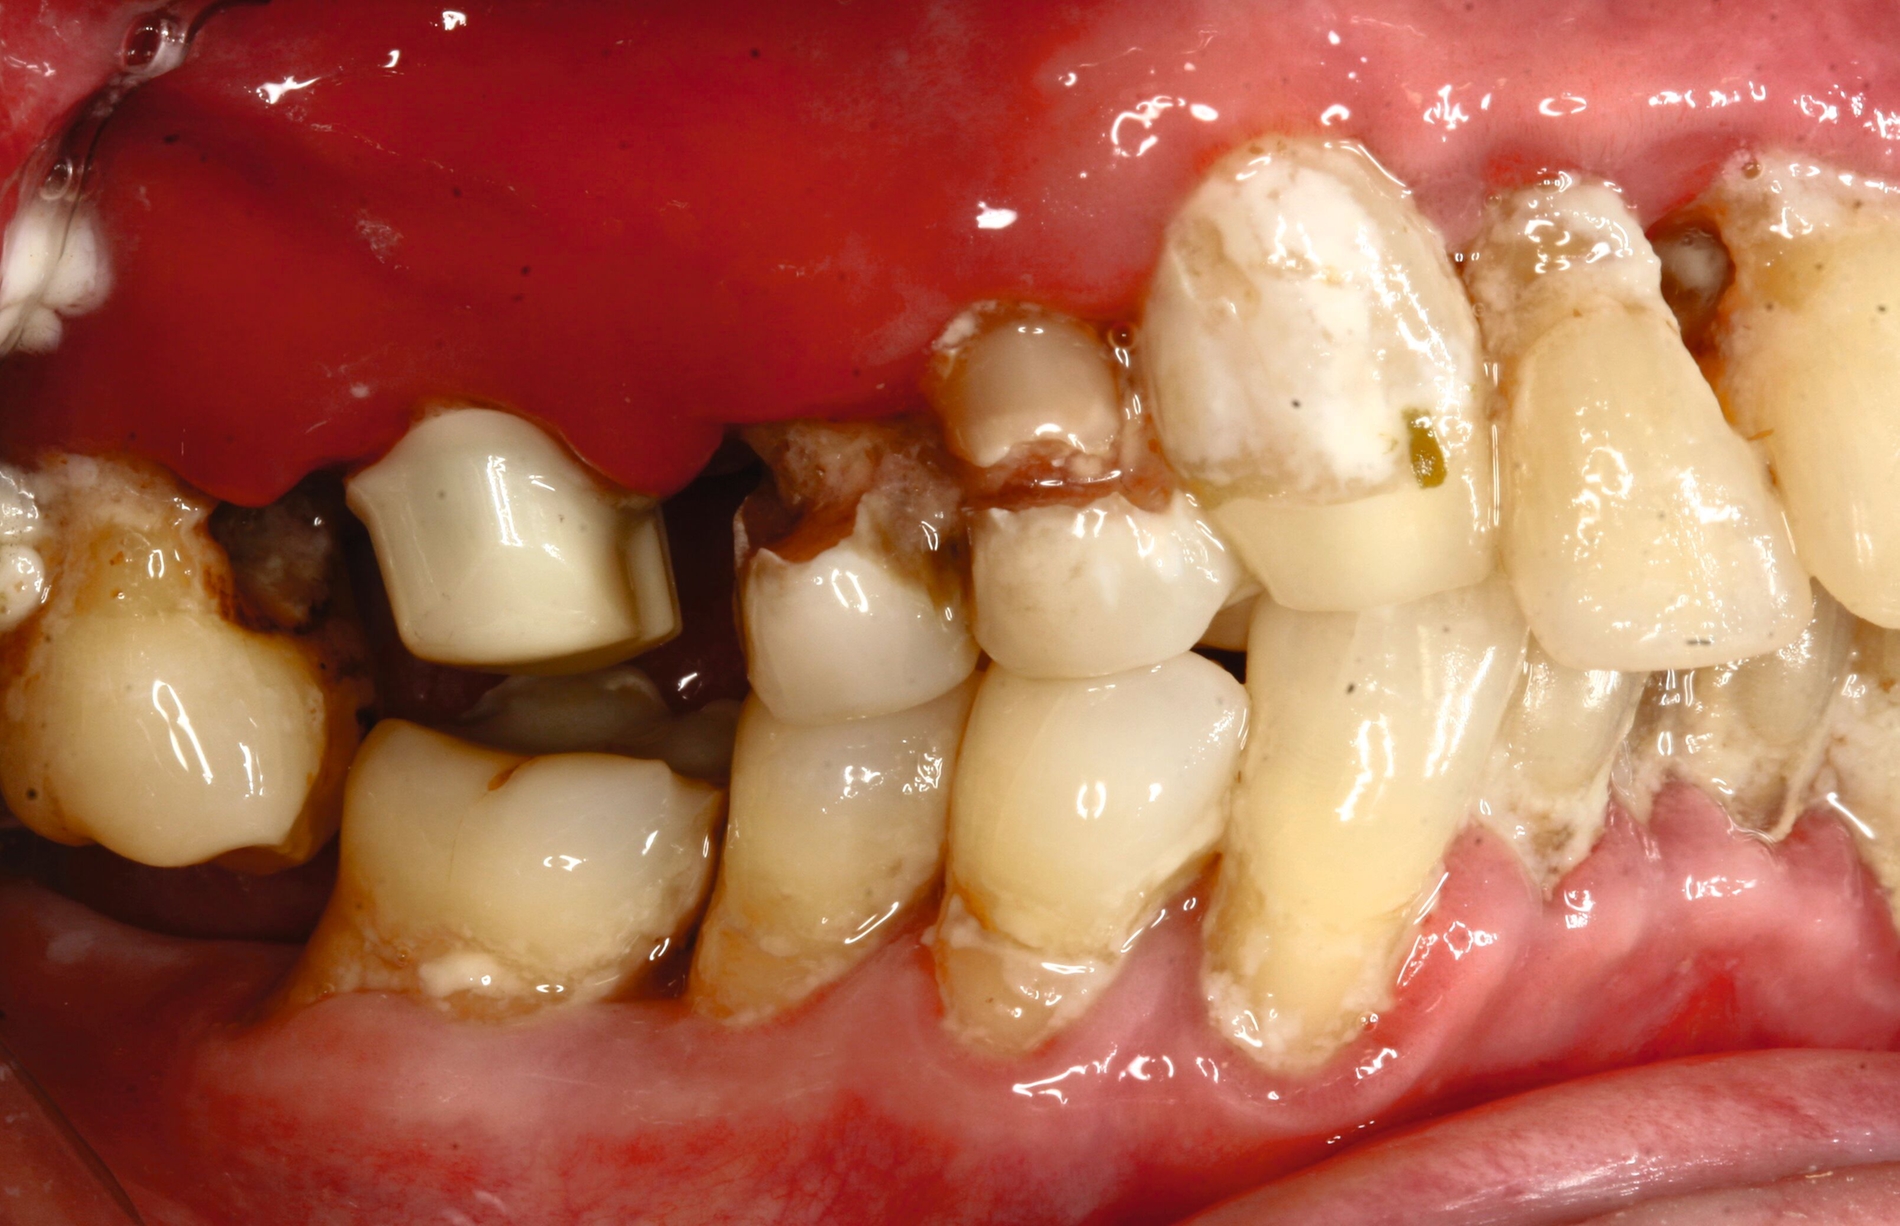

Nach siebenjähriger Tragezeit reduzierte sich der Allgemeinzustand der Patienten bedingt durch einen zweifachen Apoplex erheblich. Die Angehörigen bemühten sich bei nun fehlender Eigenverantwortlichkeit der Patientin um eine dauerhafte Aufnahme in eine Pflegeeinrichtung. Eine Vorstellung zur zahnärztlichen Kontrolle erfolgte nicht und die Patientin konnte unter ihrer ursprünglichen Adresse nicht mehr erreicht werden. Nach eineinhalbjähriger Abwesenheit wurde die Patientin mit Unterstützung ihrer Angehörigen wegen reduzierter Nahrungsaufnahme aufgrund von Schmerzen zur zahnärztlichen Behandlung vorstellig (Abbildung 3). Bei stark reduzierter Therapie- und Mundhygienefähigkeit wurde zusammen mit den Angehörigen entschieden, mehrere stark kariös und parodontal geschädigte Zähne zu entfernen und den vorhandenen Zahnersatz umzuarbeiten. Es lag nun eine BS 3 bis 4 vor.